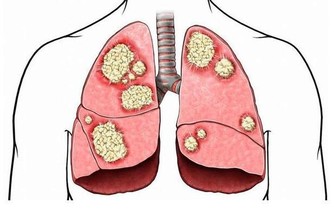

▼7. 杵狀指甲

亦稱作鼓棰指,即手指末端增生、肥厚,這可能是完全無害或源自遺傳,但如果是指甲突然開始軟化並大小不一,那代表你血液裡的含氧量低。此外,杵狀指甲有可能是肺部肝臟疾病、心臟病和炎症性腸疾病而引起的。